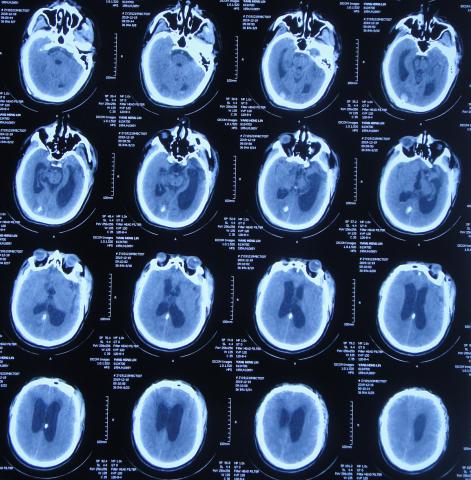

但拔除腰大池引流管后第2天就出现了发热,再次给予腰大池引流,但引流出淡红色浑浊脑脊液,且化验脑脊液示白细胞高,考虑颅内感染,脑脊液培养无细菌生长,给予抗菌素后3天后体温变正常。

第2次腰穿引流后11天即2020年1月14日,查头颅CT( 图-21 )后认为病情有好转,随后拔除腰大池引流管,计划明日第2次进行脑室腹腔分流术。

图-21: 2020年1月14日头颅CT

颅骨修补术后33天即第1次脑室分流管拔除后27天2020年1月15日,进行了第2次的脑室腹腔分流术( 图-22 )。

图-22: 2020年1月15日头颅CT

颅骨修补术后35天即第2次脑室腹腔分流术后2天2020年1月17日,病情稳定,查头颅CT( 图-23 )后认为无异常。

图-23: 2020年1月17日头颅CT

颅骨修补术后40天即第2次脑室腹腔分流术后7天即2020年1月22日(第2家医院住院治疗43天)出院,转住入第3家的北京某康复医院进行康复治疗。

在第3家医院康复治疗近1个月时间内,曾4次查头颅影像(2020年1月22日( 图-24 )、2020年1月29日( 图-25 )、2020年2月10日( 图-26 )、2020年2月19日( 图-27 ))均示脑室仍有扩张,但未给予特殊处理。

图-24: 2020年1月22日头颅核磁

图-25: 2020年1月29日头颅CT

图-26: 2020年2月10日头颅CT

图-27: 2020年2月19日头颅CT

但住院期间间断性发热仅给予药物后仍反复,且大小便时有*禁失**,因此于第3家医院治疗28天后即2020年2月19日,转回当地的第4家河北省邯郸市某三甲医院治疗。

在第4家医院治疗26天,仍间断性发热、大小便*禁失**加重,住院期间曾2次查头颅CT(2020年2月27日( 图-28 )、2020年3月12日( 图-29 ))示脑室仍扩张。

图-28: 2020年2月27日头颅CT

图-29: 2020年3月12日头颅CT

治疗期间给予抗生素,并多次腰椎穿刺,脑脊液培养示无菌,发热虽有好转但大小便*禁失**无改善,且意识变模糊。经当地医生介绍转住入北京北亚骨科医院的李小勇脑脊液科。